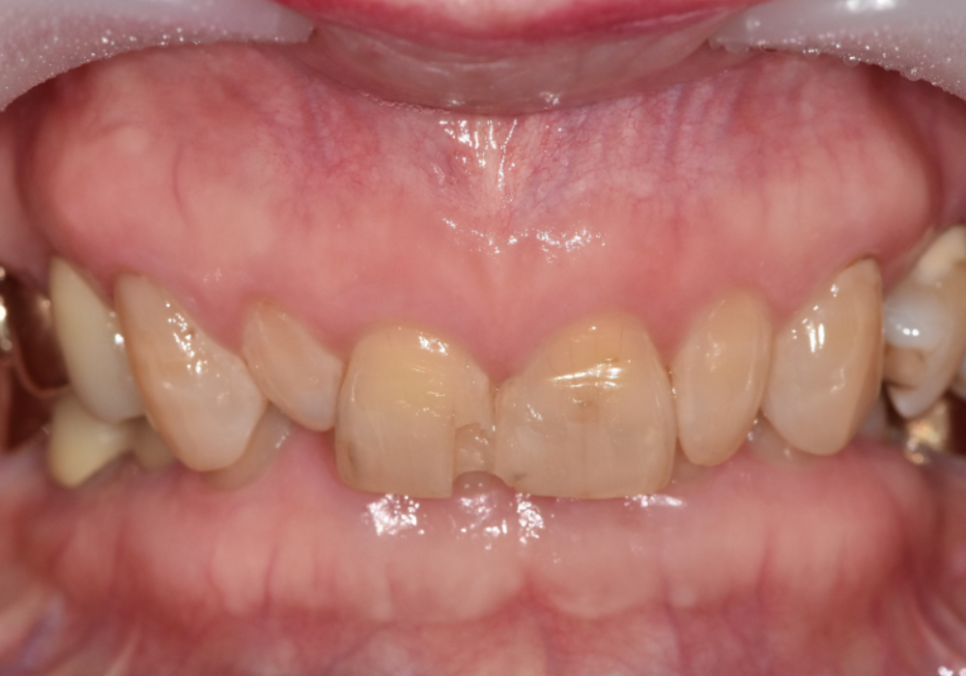

이 환자분은 70대 여성입니다.

젊을 때부터 앞니 사이가 벌어져 있었고

그 틈을 레진으로 메워 사용해 오셨다고 해요.

처음에는 괜찮았지만 나이가 들며

레진이 깨지고 떨어지는 일이 반복되자

“이번에는 제대로 고쳐보고 싶다”며 내원하셨습니다.

입안을 자세히 보니

앞니 사이를 메운 레진이 깨져 있었고,

그 양옆 작은 앞니가

다른 치아보다 눈에 띄게 작았습니다.

이렇게 주변 치아보다 유난히 작은 치아를

‘왜소치’라고 부릅니다.

왜소치는 크기가 작다 보니

그 주변으로 공간이 남기 쉽고,

결국 앞니 사이가 더 벌어져 보이는 원인이 됩니다.